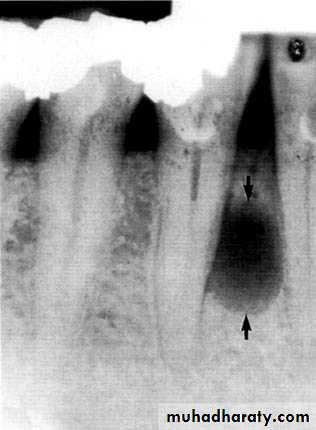

Radiolucency at apex of endodontically treated tooth

A: Radiolucent apical scar left after successful endodontic treatment..

B:New bone forming from the periphery of theLesion.

If the R.L.enlarged, pain,sinus,or no regression in the size of lesion after 6months (P. A. Cyst).

Apical scar